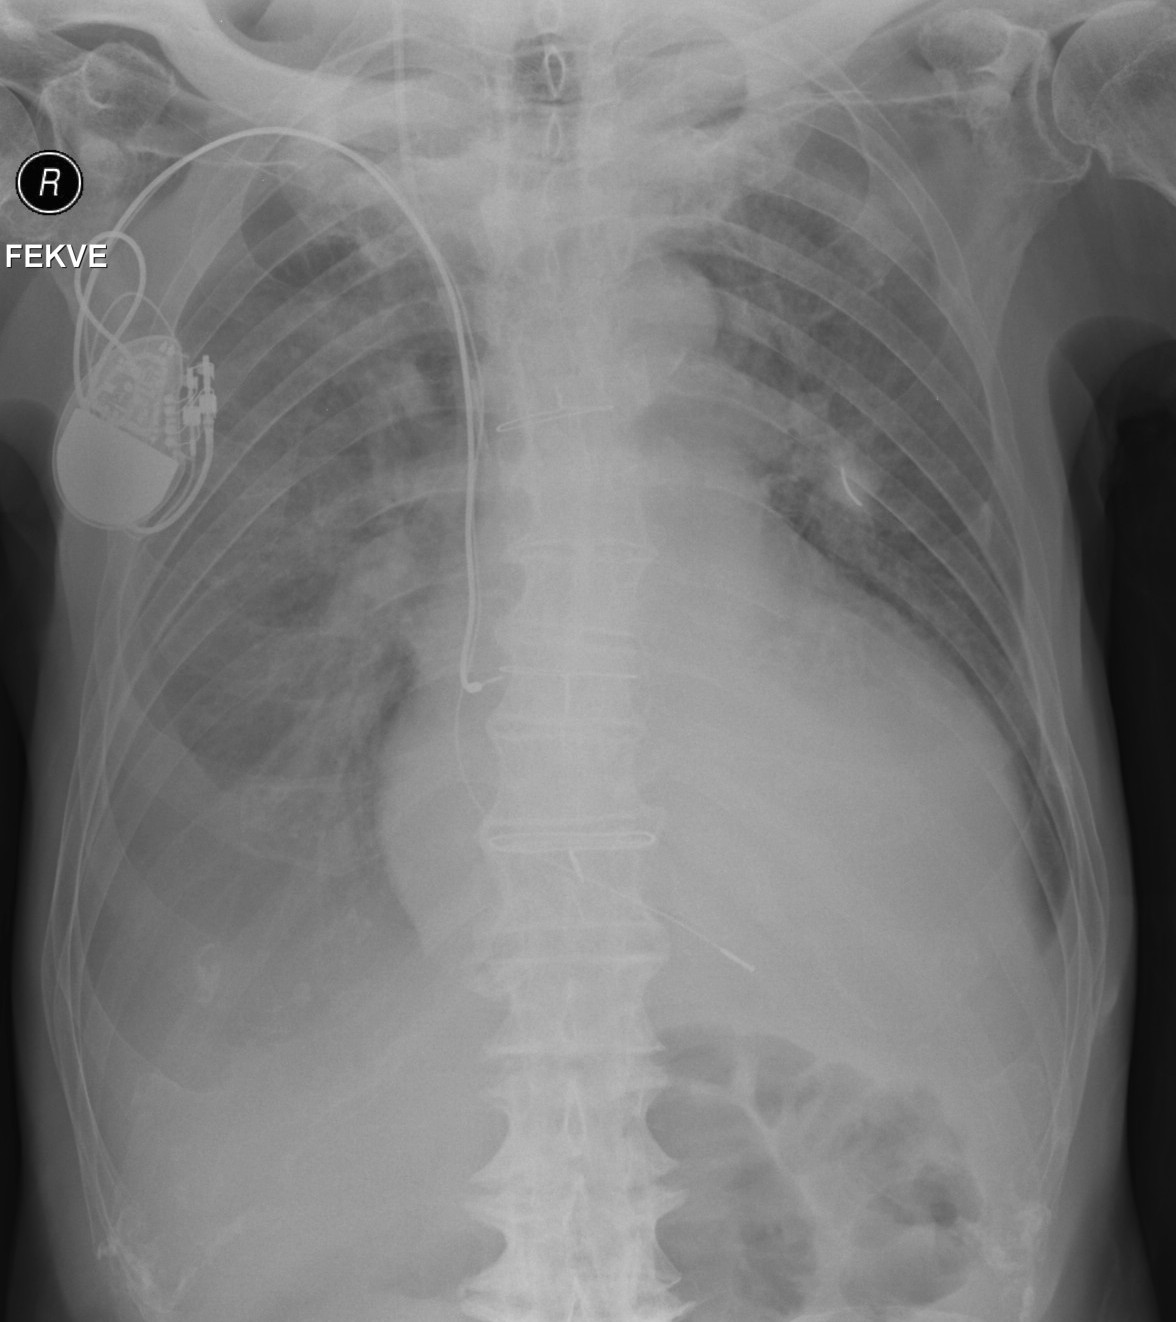

28. Pleural effusion (+ foreign body), AP chest radiograph, supine.

85 year old man. No differenciation of diaphragm is possible on both sides. Basal lung areas: hypolucency. Along the right lateral chest wall, mild hypolucent streak can be observed extending to the apex (fluid).

Remarkable left cardiomegaly, almost reaching the lateral chest wall.

Pacemaker + its electrodes on the right side. The end of the right internal jugular vein catheter ends at the projection of the superior vena cava. At the projection of the anterior arch of the left 3rd rib a 1.5 cm large arched shadow can be seen in metal intensity in the medioclavicular line (6-7 cm long, thin, linear metal foreign body)